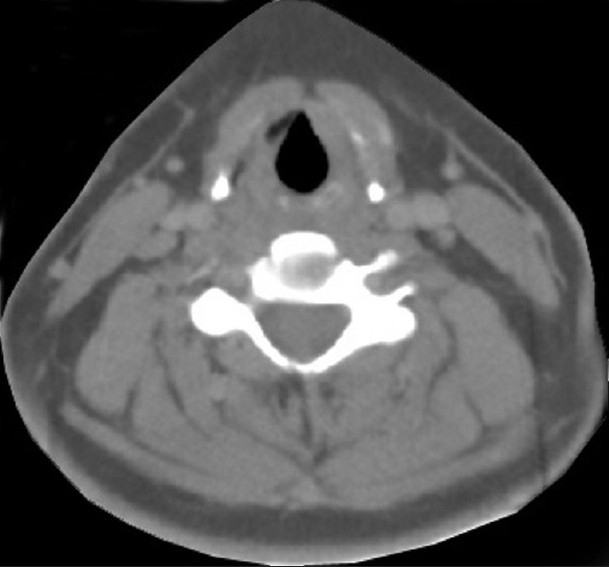

A 16-year-old female patient presented to the radiotherapy department in July 2008 with complaint of unrelenting hoarseness of voice for the last 1 year. She developed it gradually over a period of time. Initial treatment was directed to common cold but was of no help. There was no associated sore throat, otalgia, localized pain or tenderness over thyroid cartilage, dysphagia or features of airway obstruction. The patient is a nonsmoker and is nonalcoholic and without any history of past or present marijuana smoking. There was no history of prior neck irradiation. An incidence of cancer in the family could not be elicited from a detailed history. An indirect laryngoscopy was performed, which showed both vocal cords to be mobile. There was no visible growth over any of the vocal cords. Contrast-enhanced CT scan of the neck was performed, and it showed a small irregular lesion over the left vocal cord at the junction of anterior one third and posterior two thirds [Figure 1]. Thickening of left true vocal cord with loss of paraglottic fat is seen, suggestive of a neoplastic lesion. The normal paraglottic fat on the right side is seen as black area just deep to the thyroid cartilage (seen as white). The airway is seen as black oval structure. There is no visible neck node. Fiber-optic laryngoscopy confirmed the CT scan finding, which also showed irregular lesions along the medial margin of the left vocal cord [Figure 2]. Both CT scan and fiber-optic laryngoscopy showed an otherwise normal picture. Microlaryngoscopic removal of the mass was performed. Histopathological examination under low-power and high-power fields showed severe dysplasia and full-thickness replacement of epithelium with dysplastic cells and diagnosed it as carcinoma in situ [Figures [Figures33 and and4].4]. However, the risk of a micro-invasive carcinoma could not be ruled out. A second biopsy was advised to obtain deeper tissue, but it was refused by the patient. So from the available documents, we considered it carcinoma in situ of the vocal cord.

| Figure 1 CECT scan of neck showing irregular lesion along the medial margin of left vocal cord at the junction of anterior one third and posterior two thirds. There is thickening of left true vocal cord with loss of paraglottic fat, suggestive of a neoplastic lesion. The normal paraglottic fat on right side is seen as black area just deep to the thyroid cartilage (seen as white). The airway is seen as black oval structure